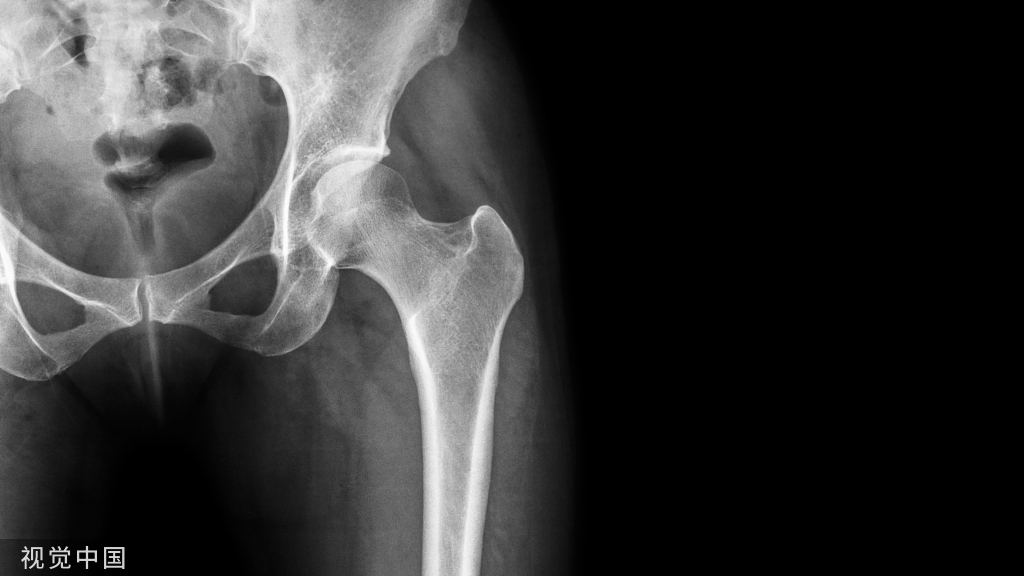

​骨质疏松症是一种以骨量低下,骨微结构损坏,导致骨脆性增加,易发生骨折为特征的全身性骨病,今天是世界骨松日,让我们学习一下这个“寂静”的杀手!

骨质疏松症( osteoporosis,OP)是一种以骨量低下,骨微结构损坏,导致骨脆性增加,易发生骨折为特征的全身性骨病

如果把骨骼比作房子,有墙壁、大梁、承重墙等,骨质疏松了,房子的墙壁有损坏了、有些大梁断裂了、房子容易坍塌。